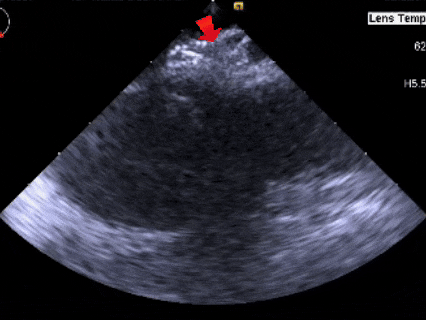

成型锁定

鞘管抵住封堵器后,前顶钢缆,

固定钢缆和鞘管,牵拉成型线锁定

锁定后牵拉试验

锁定后,封堵器形态良好,进行牵拉试验,

超声下可见封堵器整体移动,右盘面未被拉开